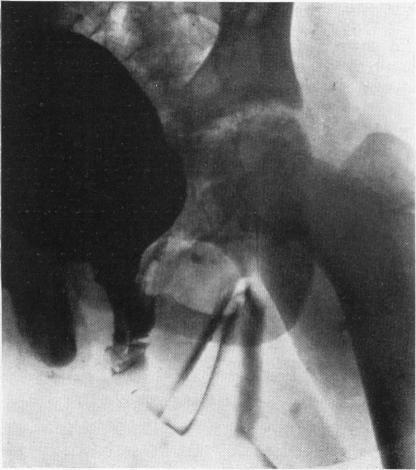

FISHER O D, FORSYTHE W I

Arch Dis Child. 1954 Oct;29(147):460-71. doi: 10.1136/adc.29.147.460.